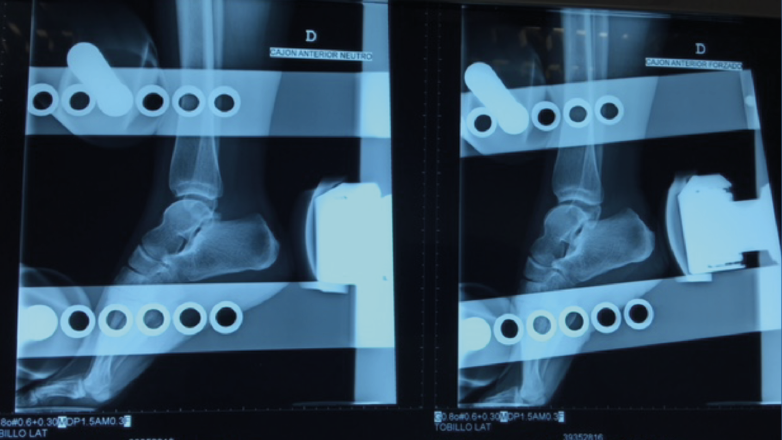

– Cajón anterior: paciente sentado con la rodilla en flexión. Aplicando rotación interna se testa el ligamento peroneo-astragalino anterior (PAA); con rotación externa valoramos la laxitud medial (frecuentemente asociada a dolor anteromedial)(Figura 2).

- Cajón anterior: positiva si existe una traslación anterior > 1 cm o una diferencia > 3 mm respecto al tobillo contralateral (Figura 4).

Figura 2. Maniobra del cajón anterior. Paciente sentado con la pierna colgando a 90°. El cajón anterior con tope óseo pone de manifiesto la insuficiencia del ligamento peroneo-astragalino anterior.

Figura 4. Radiografía del cajón anterior. El cajón anterior es positivo si existe una traslación anterior > 1 cm o una diferencia > 3 mm respecto al tobillo contralateral.